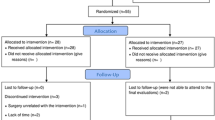

We recruited 51 female FM patients aged 18 to 65 years, who fulfilled the American College of Rheumatology 1990 diagnostic criteria for FM1, through Helsinki University Hospital (HUH) outpatient clinics, City of Vantaa Health Centre, and the private clinic of one of the authors (RM). Thirty-one healthy, age- and gender-matched controls were also recruited. We recruited the maximum number of patients and matched volunteers available during the funding period of the study and the resulting number was similar to previous studies11,12,13,14. The exclusion criteria were: diabetes, heart disease, uncontrolled hypertension, peripheral atherosclerotic disease, neurological, neuromuscular or muscle disease, severe psychiatric disorders, continuous use of beta-blockers, beta-agonists, or statins, any musculoskeletal condition that would prevent participation in cycle ergometry (which was to be conducted at a later stage), and poor Finnish language skills that would affect the ability to answer the questionnaires. The patient selection process has been described in detail earlier16.

Between November 2015 and June 2018, the subjects visited the HUH Pain Clinic where the diagnosis of FM was confirmed for the patients and excluded for the controls through interview and clinical examination by the same author (TZ). The questionnaires used were completed by the subjects before the measurement protocol described below. We registered our study retrospectively to ClinicalTrials.gov (NCT03300635) on 03/10/2017.

As previously reported, the FM patients and controls did not differ in age (mean [SD] 45.1 [12.7] vs 46.0 [11.7] years; p = 0.785), but the FM patients had higher BMI (28.2 [5.87] vs 24.7 [3.27] kg/m2; p = 0.008) and a tendency to be less physically active (physically active n = 20 [39.2%] vs 16 [51.6%]; p = 0.386) and to smoke (smokers 12 [23.5%] vs 2 [6.5%]; p = 0.091)16.